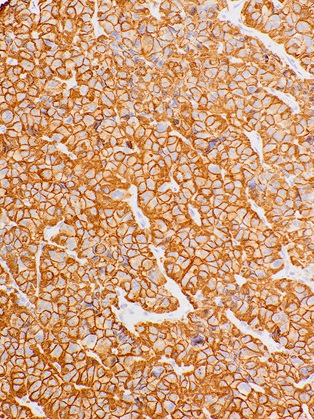

Immunohistochemical staining of human pituitary tissue using Growth Hormone (GH) Mouse Monoclonal Antibody (ARM502).

Growth Hormone (GH or hGH) is a peptidic hormone produced by somatotrophs of the anterior pituitary gland. Anti-Growth Hormone stains somatotrophs in normal pituitary tissues, and is useful in identifying pituitary tumours and understanding pituitary disease or acromegaly. Studies have also found Anti-GH to stain non-pituitary cells, such as hepatocellular carcinoma and cutaneous lesions.